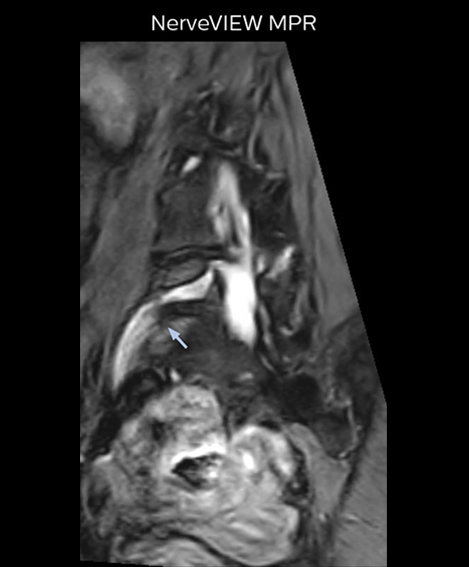

“In such case, we would then browse through axial T2-weighted MR images slice by slice and mentally reconstruct the actual situation based on both radiculography and MRI. Fortunately, NerveVIEW can now very well show nerve courses and presence of nerve compression or edema in one single image series.” “We have often seen NerveVIEW directly depict details of the nerve compression that were not observed by radiculography. Therefore, we think that with NerveVIEW we can reduce the number of invasive examinations, especially for some patients with lumbar plexus symptoms.”

“Before NerveVIEW, diagnosis by MRI alone was sometimes difficult, unless there was a strong suspicion based on clinical symptoms,” says Shoji Yabuki, MD, DMSc, Orthopedic surgeon at Fukushima Medical University School of Medicine. “This is why we routinely perform selective lumbosacral radiculography (nerve root block) and x-ray in such cases. However, radiculography can only depict nerves as far as the contrast agent reaches. When a nerve is distorted by compression, the contrast agent will not pass through this compressed area, preventing us from evaluating the full nerve compression.”

The key concept in MR neurography, Dr. Yabuki stresses, is the ability to directly visualize spinal nerves, versus inferring the presence of pathology indirectly. “Before NerveVIEW, we estimated compression of the nerve by looking for the presence or absence of fat signal on other MR images,” he says.

“For example, in sagittal images, when the presence of fat is observed in the intervertebral foramen, it suggests that there is a margin around the nerve. Similarly, the absence of fat indicates that the nerve is being compressed. So, we used to deduce nerve compression indirectly. With NerveVIEW, however, we can observe the condition of the nerves directly, regardless of the presence or absence of fat. We always prefer such direct observation of anatomy over having to make an inference about it.”

“Although symptoms of typical disc herniation and atypical hernia are very similar, the actual site of herniation is different. It is therefore important to characterize the nerve’s condition both inside and outside of the intervertebral foramina. “Conversely, if we see no abnormality in NerveVIEW, we can assume at least that there is no severe condition that requires surgery. Like this, it can help us avoid unnecessary surgery. NerveVIEW can have a tremendous impact in this way.”

“NerveVIEW is really useful for those cases where a nerve disorder is strongly suspected based on the clinical examination but our regular MRI images do not show any findings. These atypical herniations and spinal canal stenosis, occurring in 5% to 15% of the total lumbar herniation/stenosis cases are our main target when using NerveVIEW,” says Dr. Yabuki.